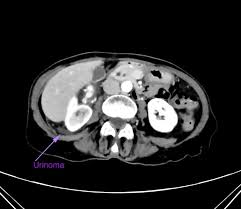

Obstructing Renal Stone With Collecting System Rupture Radiology Case Radiopaedia Org